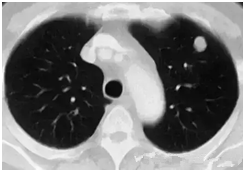

肺部小結(jié)節(jié)通常是指影像檢查(X線或者CT)中發(fā)現(xiàn)的直徑≤2cm的類圓形病灶,≤3cm的稱為結(jié)節(jié),>3cm的稱為腫塊。

也有學(xué)者認(rèn)為,分得太細(xì)并無意義,例如2.2cm的結(jié)節(jié)與1.9cm的小結(jié)節(jié),臨床上并沒有本質(zhì)的區(qū)別。在這里我們統(tǒng)一把≤3cm的結(jié)節(jié)統(tǒng)稱為肺部小結(jié)節(jié),在肺部小結(jié)節(jié)中,60%—70%為良性結(jié)節(jié),30%—40%的結(jié)節(jié)方為惡性結(jié)節(jié),所以,發(fā)現(xiàn)肺部小結(jié)節(jié)切勿驚慌。

結(jié)節(jié)的大、小與良、惡性有一定的相關(guān)性,當(dāng)肺部結(jié)節(jié)>3cm的病灶多為惡性,而微小的結(jié)節(jié),良性的可能性居多。

我們常看到的影像學(xué)描述中的“磨玻璃結(jié)節(jié)(GGO)”,其中一部分是非典型腺瘤樣增生(AAH)或原位腺癌(AIS),結(jié)節(jié)內(nèi)部的實(shí)變與生長速度的加快(范圍變大)常意味病變性質(zhì)的轉(zhuǎn)變,可以逐步演變?yōu)槲⒔櫹侔∕IS)、浸潤性腺癌(IAC)。